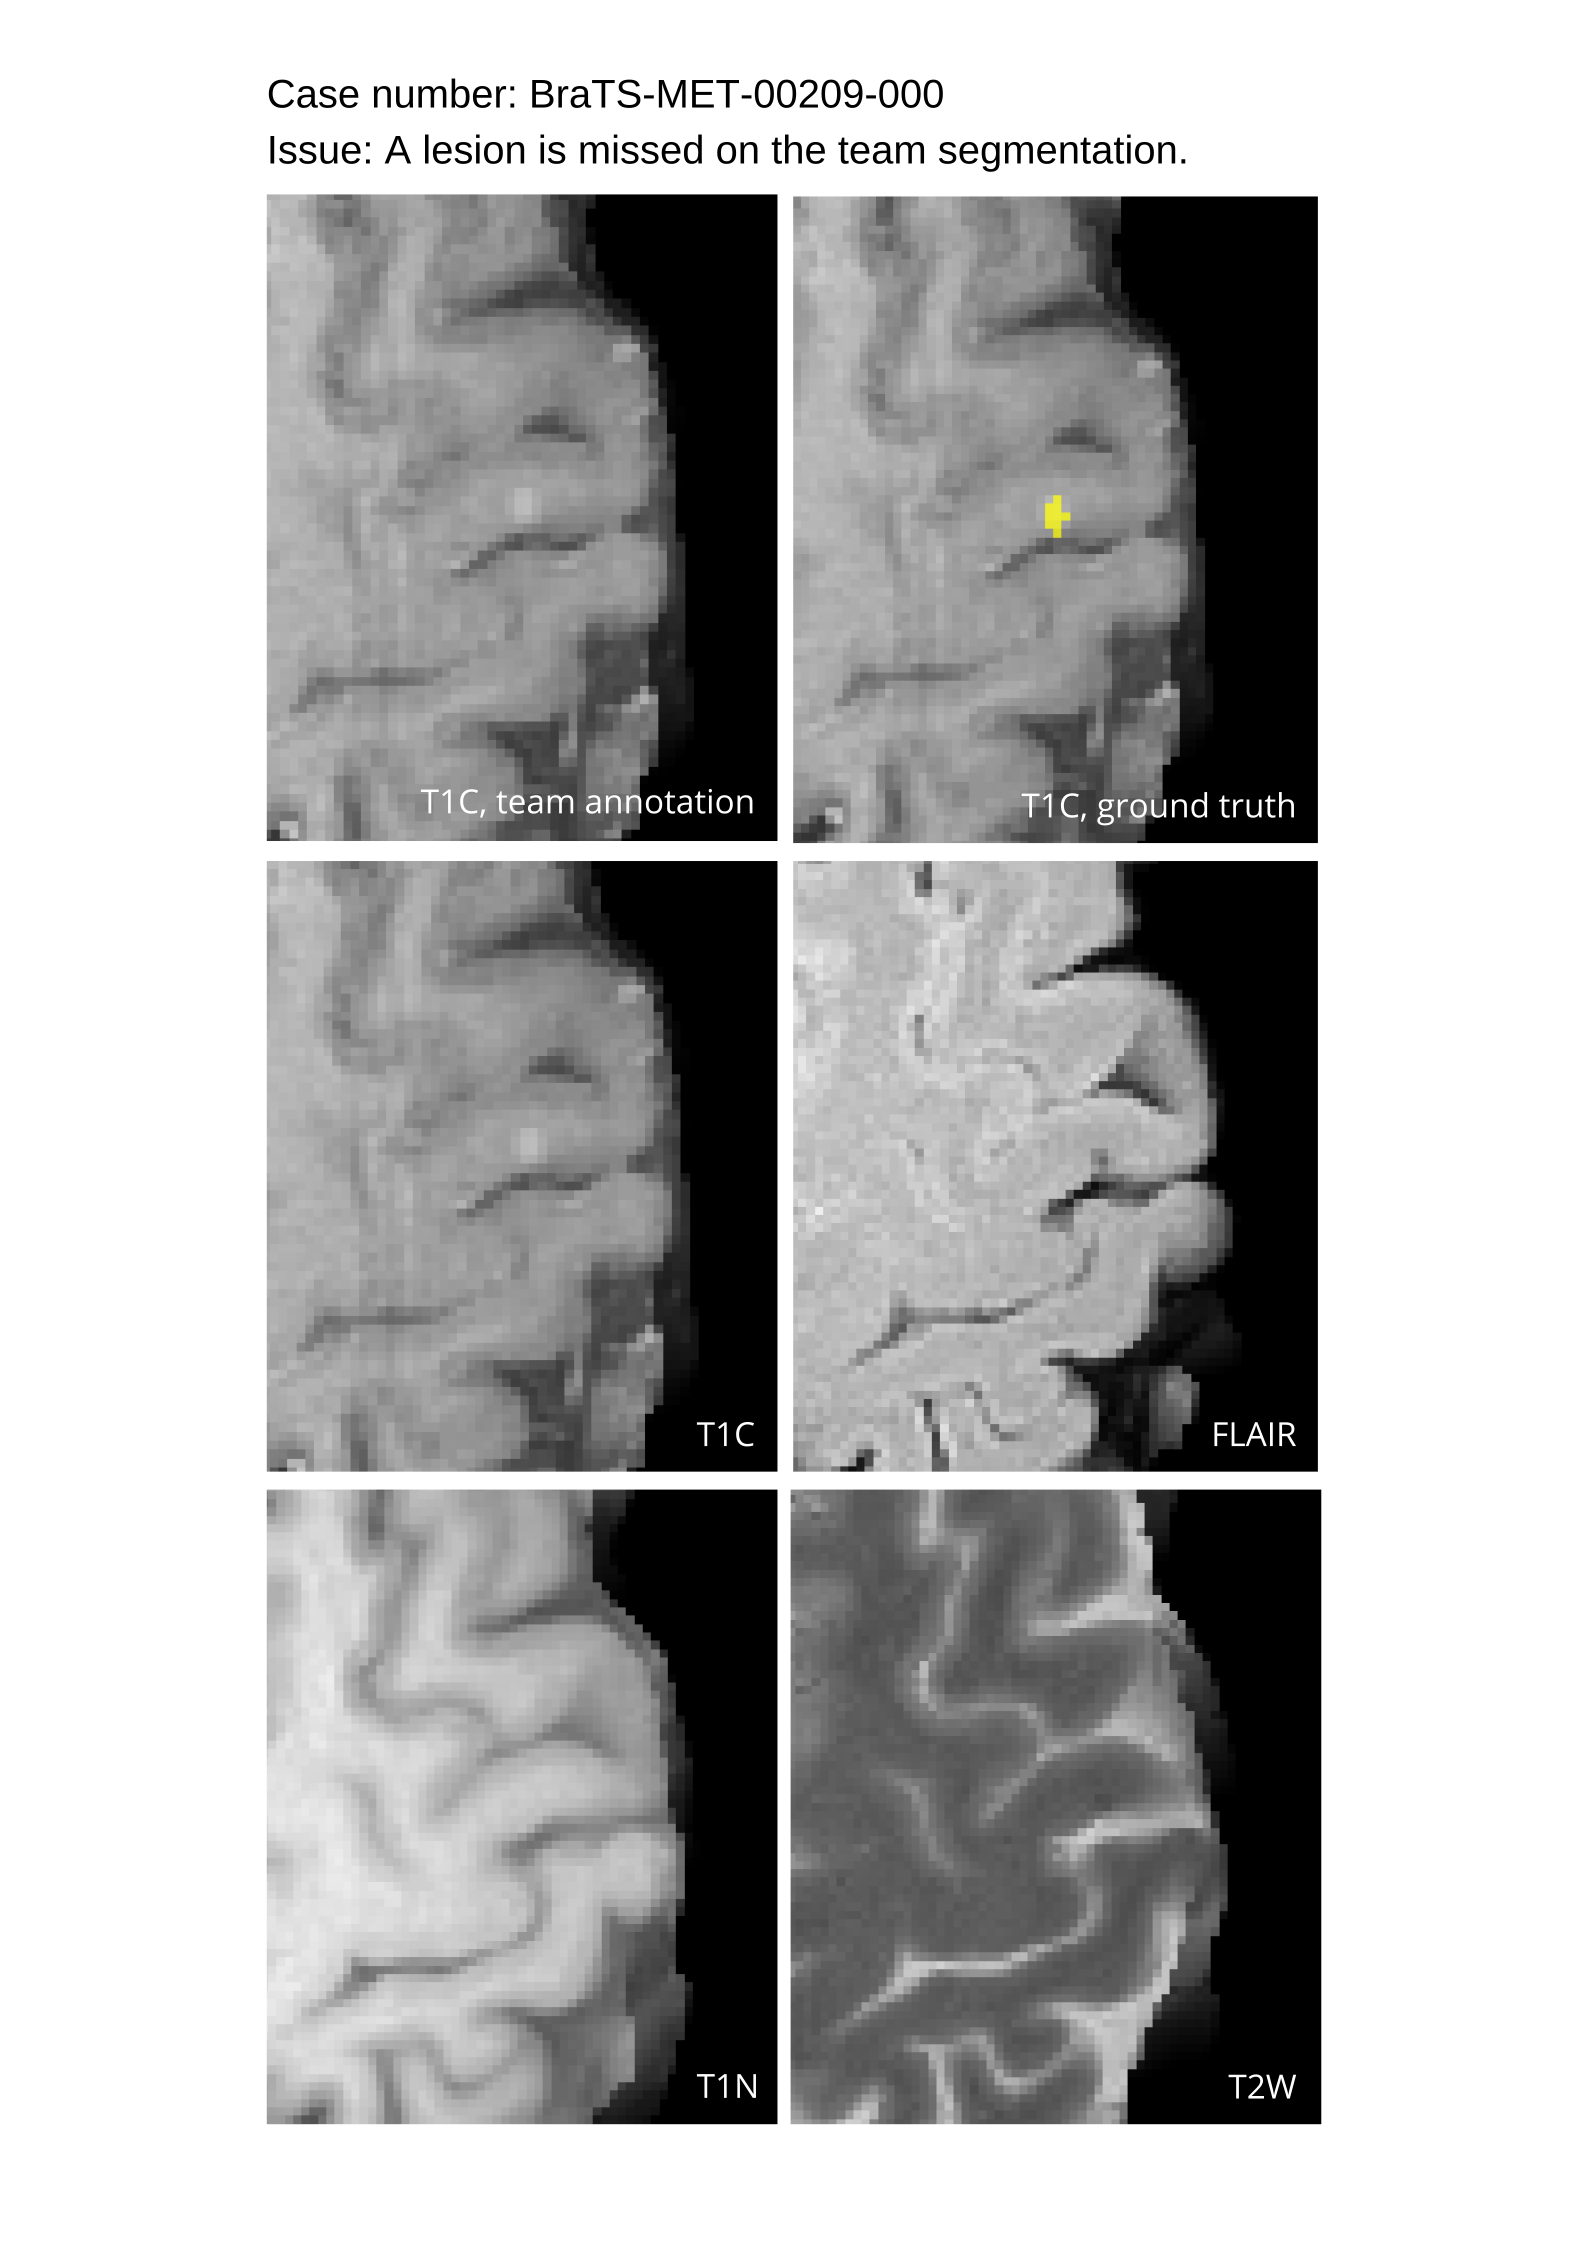

4.9 Common Errors of Automated Segmentations

Based on observations from previous BraTS challenges, common errors in automated segmentations were identified. The most typical errors in the current challenge included:

1. 1.

Automated algorithms missing small metastases. Enhancing metastasis was fused using the minority voting algorithm to aggregate all enhancing tumor voxels identified by the three algorithms. However, many small metastases were missed and were manually segmented by neuroradiology attendings.